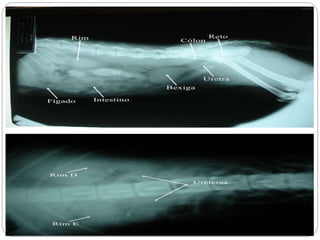

Radiografias